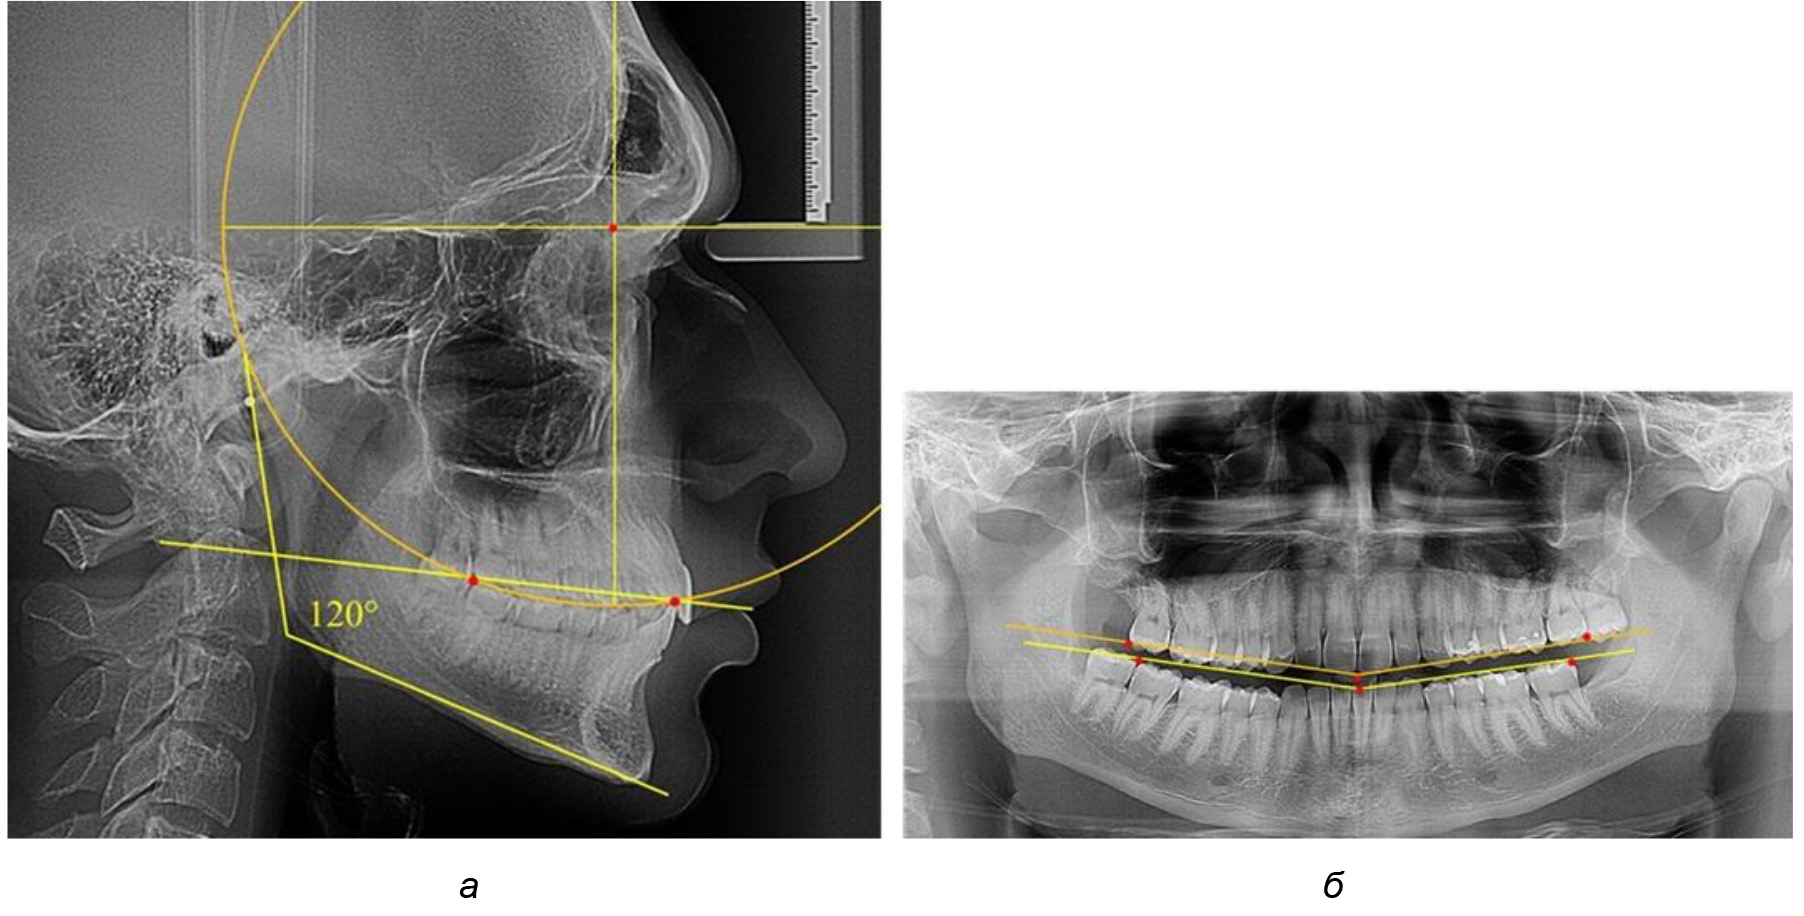

В 3-ю подгруппу вошли ТРГ и ОПТГ 14 человек 1-й группы, что составило (22,58 ± 5,31) % от общего количества людей 1-й группы. Величина угла нижней челюсти в среднем составила (114,85 ± 2,87)° и характеризовала горизонтальный тип нижней челюсти.

Глубина кривой Spee в среднем по 2-й подгруппе составил (2,94 ± 0,47) мм, что было меньше, чем в других подгруппах. Деление величины радиуса круга к длине окклюзионной линии составило 1,616 ± 0,02 (рис. 4).

Рис. 4. Особенности кривой Spee на ТРГ (а) и ОПТГ (б) у людей с горизонтальным типом лица

Таким образом, проведенное лечение техникой «прямой» дуги способствует нормализации окклюзионного равновесия и торку передних зубов, однако не соответствует оптимальному окклюзионному статусу, характеризующему физиологическую окклюзию. При этом величина нижнечелюстного угла оставалась на прежнем уровне (рис. 5).

Рис. 5. Особенности ТРГ при патологической кривой Spee до лечения (а) и после лечения (б) техникой «прямой» дуги

После лечения пациентов техникой «прямой» дуги, так же как и в 1-й подгруппе, было отмечено увеличение сагиттального размера окклюзионной лини в среднем на (2,38 ± 0,83) мм. Окклюзионная линия практически касалась окклюзионного контура всех жевательных зубов, и отмечалось практически полное отсутствие кривой Spee, так же как и у людей 1-й подгруппы 2-й группы (рис. 6).

Рис. 6. Особенности ТРГ при оптимальной кривой Spee до лечения (а) и после лечения (б) техникой «прямой» дуги

Таким образом, проведенное лечение техникой «прямой» дуги способствует нормализации окклюзионного равновесия и торку передних зубов, однако не соответствует оптимальному окклюзионному статусу, характеризующему физиологическую окклюзию. При этом величина нижнечелюстного угла оставалась на прежнем уровне.